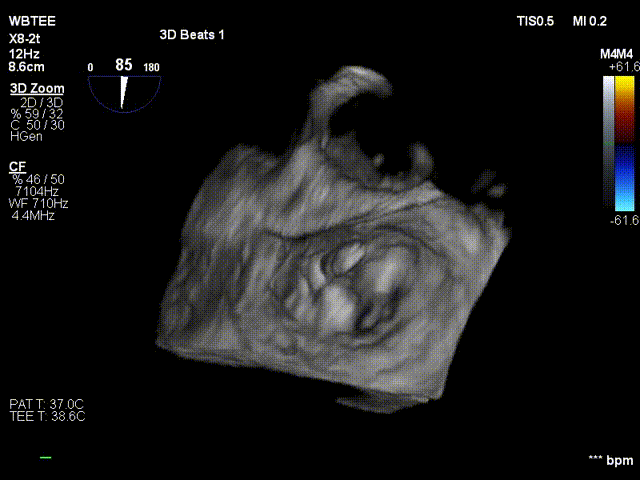

术前行经食道超声评估

原发性二尖瓣反流,反流程度4+;二尖瓣瓣口面积4.15cm²,平均跨瓣压差5mmHg,二尖瓣前叶(A2)长度23.35mm,二尖瓣后叶长度(P2)长度13.2mm;左室射血分数67%。患者手术风险高,操作难度大,经心脏瓣膜团队多次充分讨论评估后,决定行经导管二尖瓣缘对缘修复治疗。

术前MDT策略:从解剖结构来看二尖瓣后叶脱垂伴连枷涉及整个2区,累及3区和1区,宽度15mm左右,且连枷高度甩起高度有7-8mm,可见长达10.4mm的飘样回声,术前策略预计使用两个二尖瓣夹,较小的二尖瓣口面积和较高平均跨瓣压差,是一次高难度的挑战。